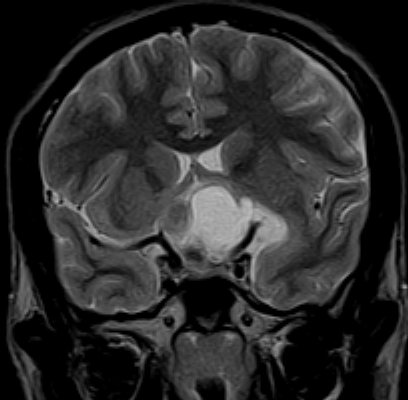

December 2005 - Craniopharyngioma

There is evidence of a lobulated extra-axial mass lesion in the suprasellar cistern. The lesion is predominantly hyperintense on the T1W images and heterogeneously hyperintense on the T2W and FLAIR images. The optic chiasm, proximal optic nerves and the pituitary stalk cannot be identified separately from this lesion. However, the pituitary gland is well identified.

Craniopharyngiomas are epithelially derived neoplasms that usually occur in the suprasellar cistern. Occasionally they occur in the sella or in the third ventricle.  They constitute approximately 3% of all intracranial tumors and show no sex predilection. Craniopharyngiomas are hormonally inactive lesions. 50% of these lesions occur in childhood or adolescence, with a peak incidence between 5 and 10 years of age. A second smaller peak is seen in the sixth decade. Patients may present with headaches and/or visual disturbances. The lesions usually exhibit a heterogeneous appearance with presence of a cystic and/or solid component. It may be hyperintense on both T1W and T2W images. The lesions may encase nearby cerebral vasculature. The solid portion may be calcified. On contrast the solid portion usually enhances.